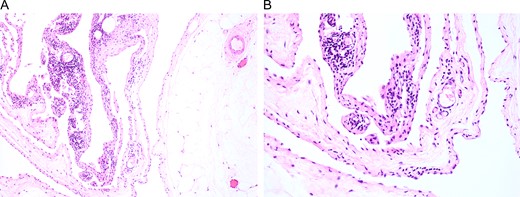

The patient was brought back to the outpatient breast center to discuss imaging results and surgical options. She elected to proceed with surgical excision of the mass given the size and its distorting nature (Fig. 2A). Due to insurance issues, the patient was unable to have immediate reconstruction with a plastic surgeon. One week later, the patient was scheduled for excision of the left breast mass (Fig. 2B and C). She tolerated the procedure well without any complications, and she was comfortable going home the same day on minimal analgesia. The final pathology report was consistent with lymphangioma (Fig. 3), showing a 21.0 × 20.0 × 6.0 cm3 mass that contained nearly 800 mL of serosanguinous fluid. The cyst wall varied in thickness from 0.1 to 0.2 cm. Post-operatively, the patient did well with no wound complications or complaints. She was referred to plastic surgery for delayed reconstruction at an outside institution.

Surgical specimens were collected and stained with H&E. Representative images are shown at (A) low and (B) high magnification, which affirmed the diagnosis of cystic lymphangioma.